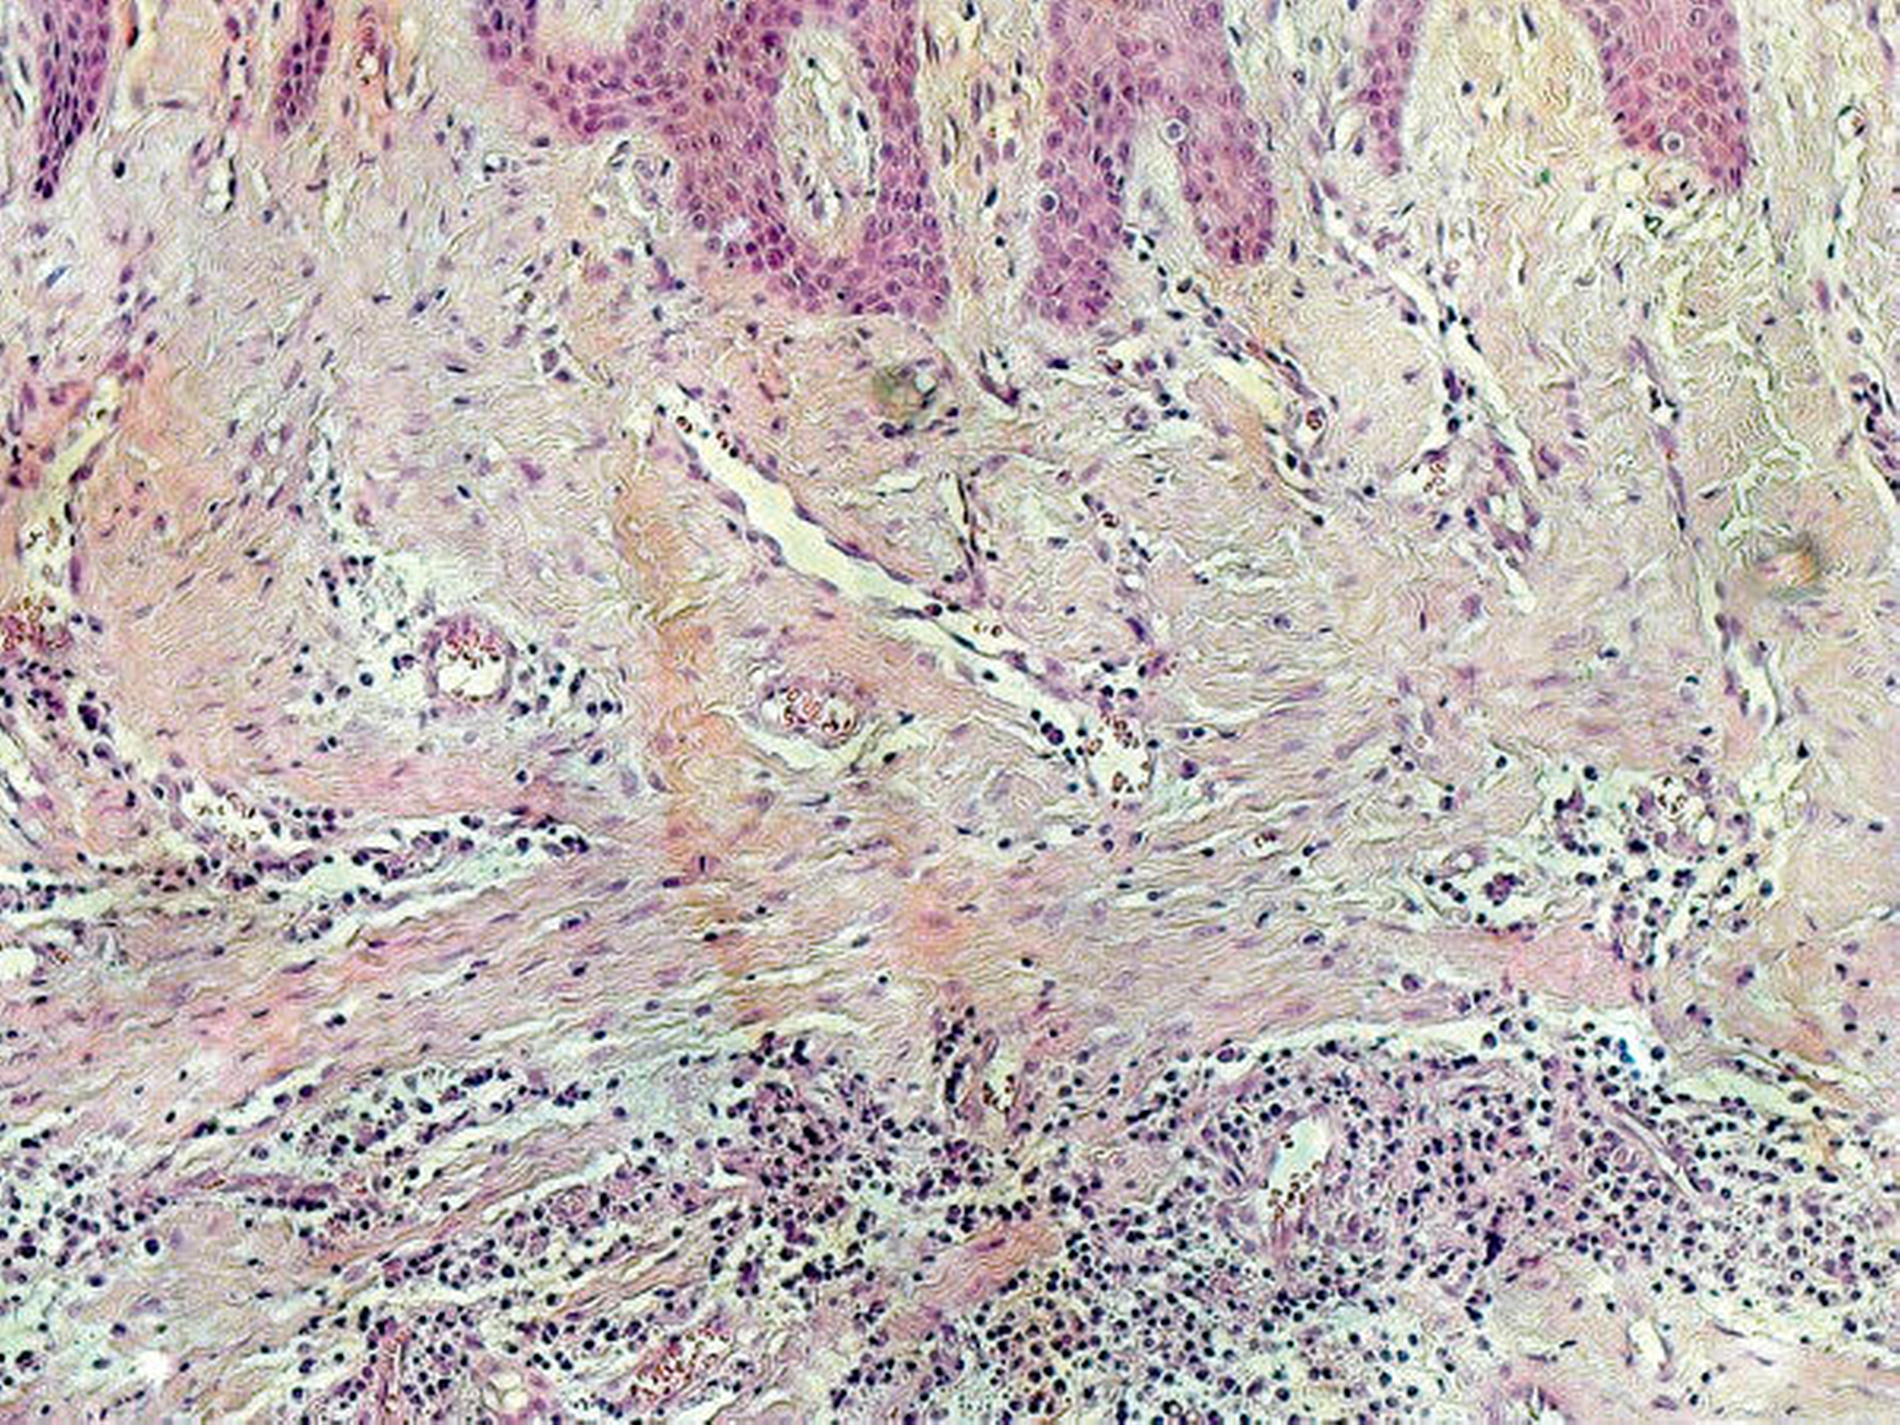

Die histologische Aufarbeitung des etwa 3 cm x 2,5 cm x 2 cm großen Resektats ergab ein spindelzelliges Proliferat mit myxoidem Stroma (Abbildung 7) und Arrosionen des ortsständigen Knochens. Zur weiteren histogenetischen Typisierung wurde ergänzend eine immunhistochemische Untersuchung durchgeführt, die die Diagnose des odontogenen Myxofibroms bestätigte. Bei einem Nachsorgeintervall von insgesamt sechs Jahren zeigte sich sowohl klinisch als auch radiologisch kein Anhalt auf ein Rezidiv.